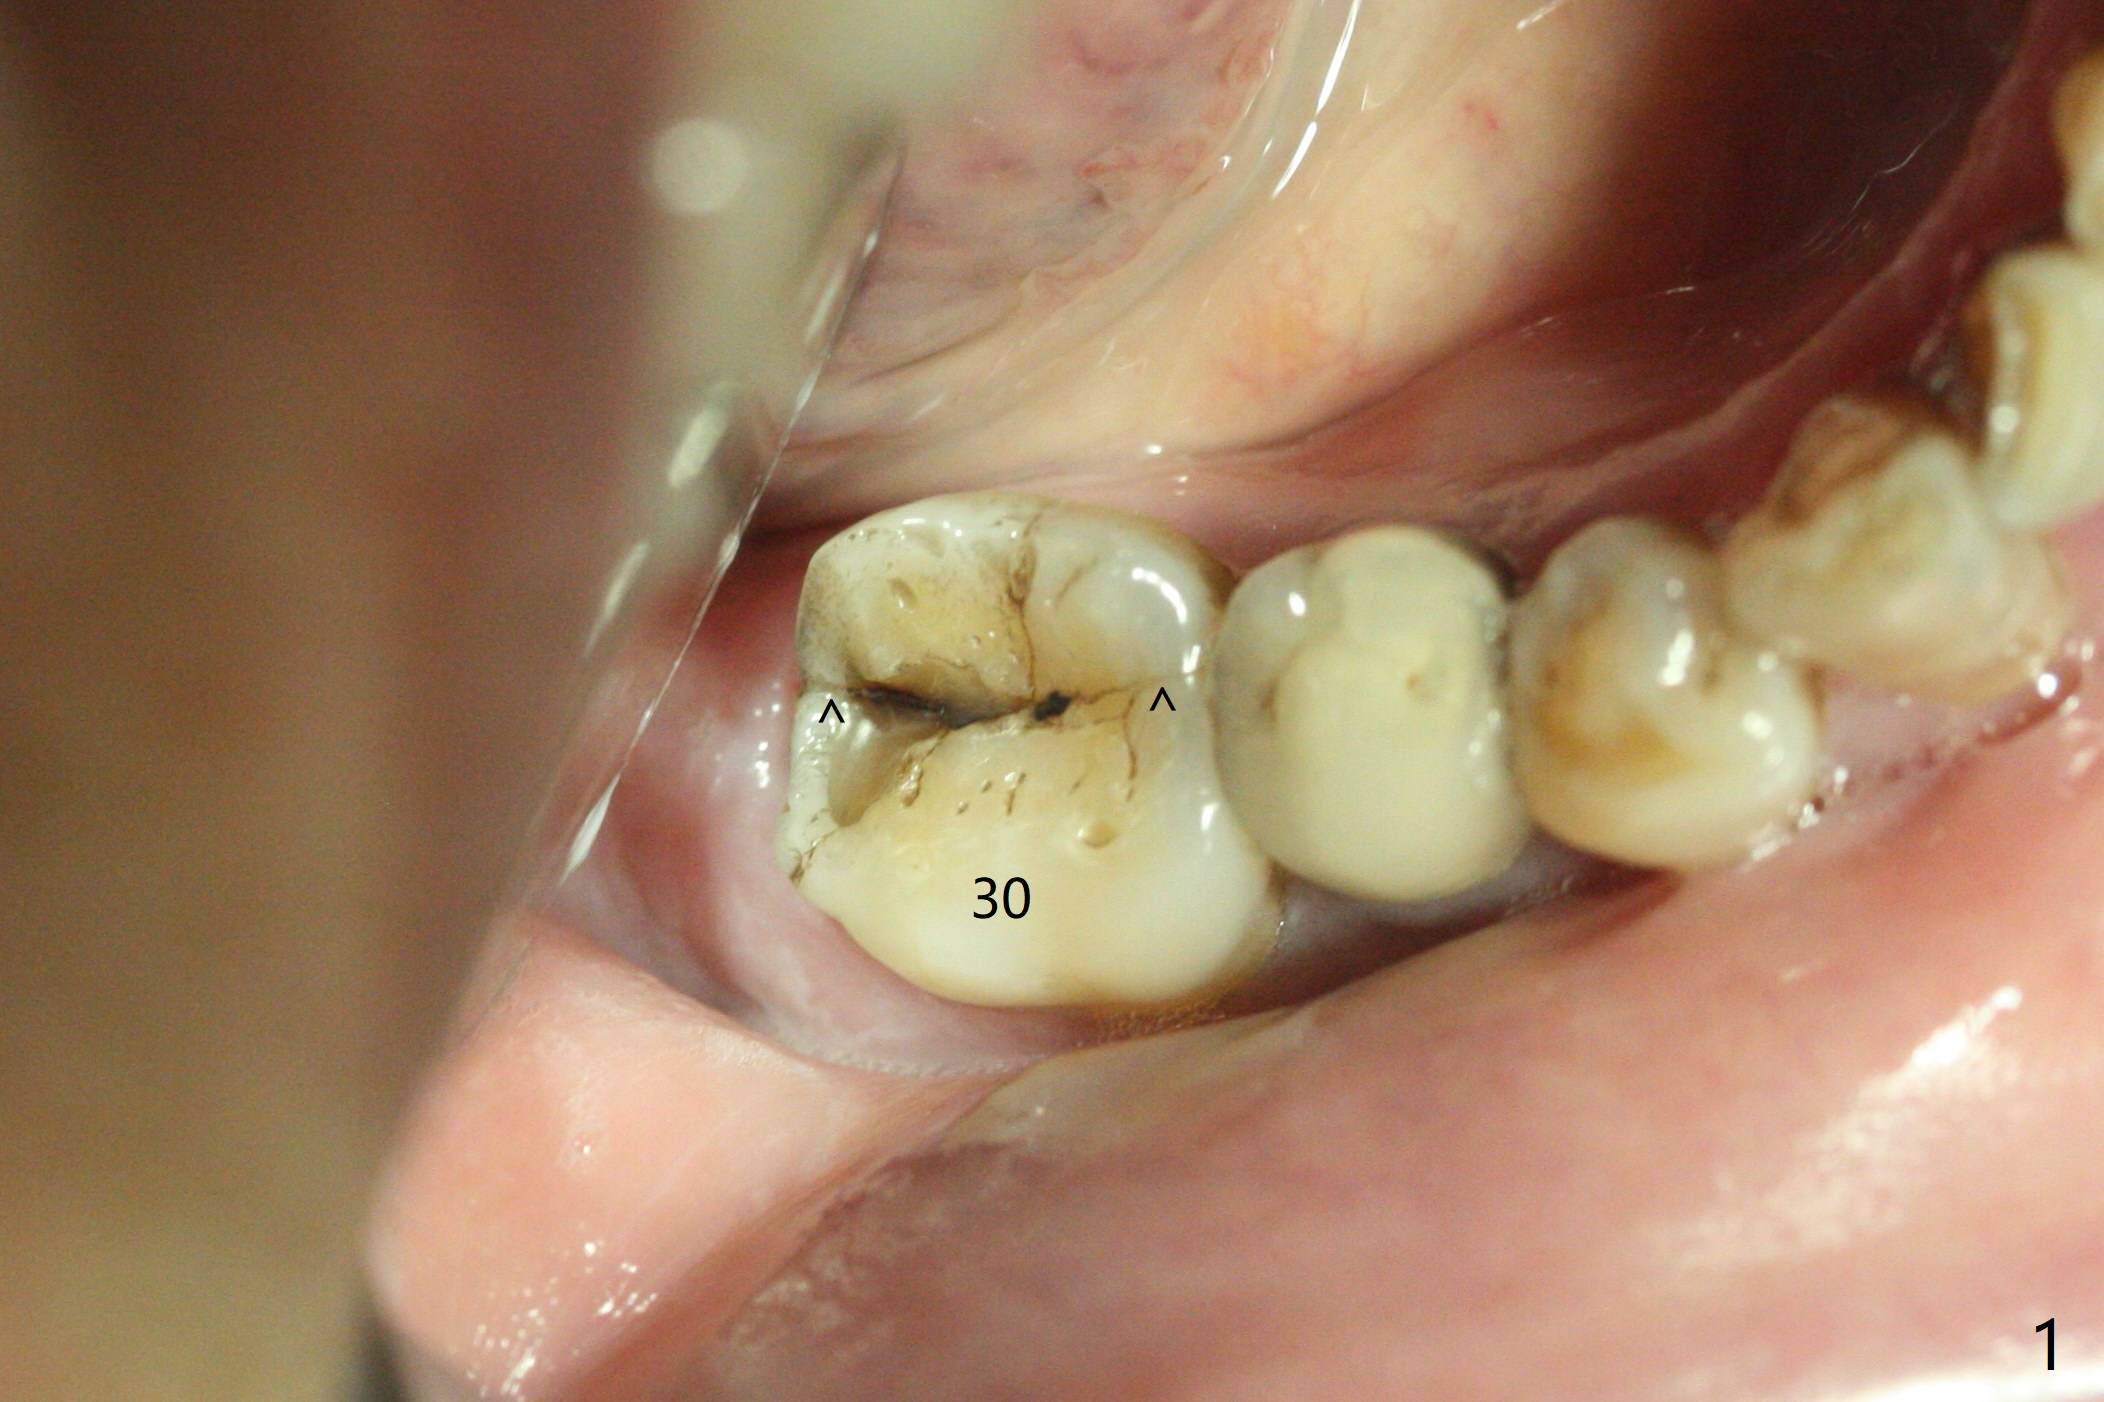

A 59-year-old woman with severe pain and mobility at #30 returns to clinic for extraction and implant on emergency basis (Fig.1 ^: crazing line). To prevent osteotomy deviation off the septum, the crown is sectioned (Fig.2) and the coronal end of the septum is exposed. In fact the initial osteotomy is blind (Fig.3). After increasing the access (Fig.4), trying to change trajectory and increasing the depth and diameter of the osteotomy, the trajectory deviates to the distal socket (Fig.5). Following root extraction, debridement of the sockets and minor trajectory change, a 4x11 mm dummy implant is placed (Fig.6). With a drastic change in osteotomy, the dummy implant position is somewhat acceptable with a 5.2x4 mm planning abutment (Fig.7 P). After placement of bone graft around the 4.5x11 mm final implant to enhance stability, a 5.5x4(3) mm definitive abutment is placed in a restorable position (Fig.8). The implant turns while the abutment screw is hand tightened. Since there is an apical space (Fig.8 <), the implant is then placed ~ 1mm deeper with ~ 30 Ncm (Fig.9). A longer cuffed abutment is inserted and more bone graft is placed (*). In summary, roots in the sockets do not seem to help free hand osteotomy in the lower 1st molar. It is also difficult to control pain during acute infection. Block anesthesia has to be administered, increasing the chance of nerve injury. Either guided surgery or delayed implant should be conducted. There is no postop paresthesia, although the buccal gingiva is slightly erythematou, edematous and tender 1 week posotp. Oral Amoxicillin is prescribed for one more week. The keratinized gingiva (Fig.10 ^) and the papilla (*) are maintained in place around the immediate provisional (P) 2 months 20 days postop. The soft tissue remains normal 4 months postop (Fig.11) and immediate pre cementation (Fig.12).